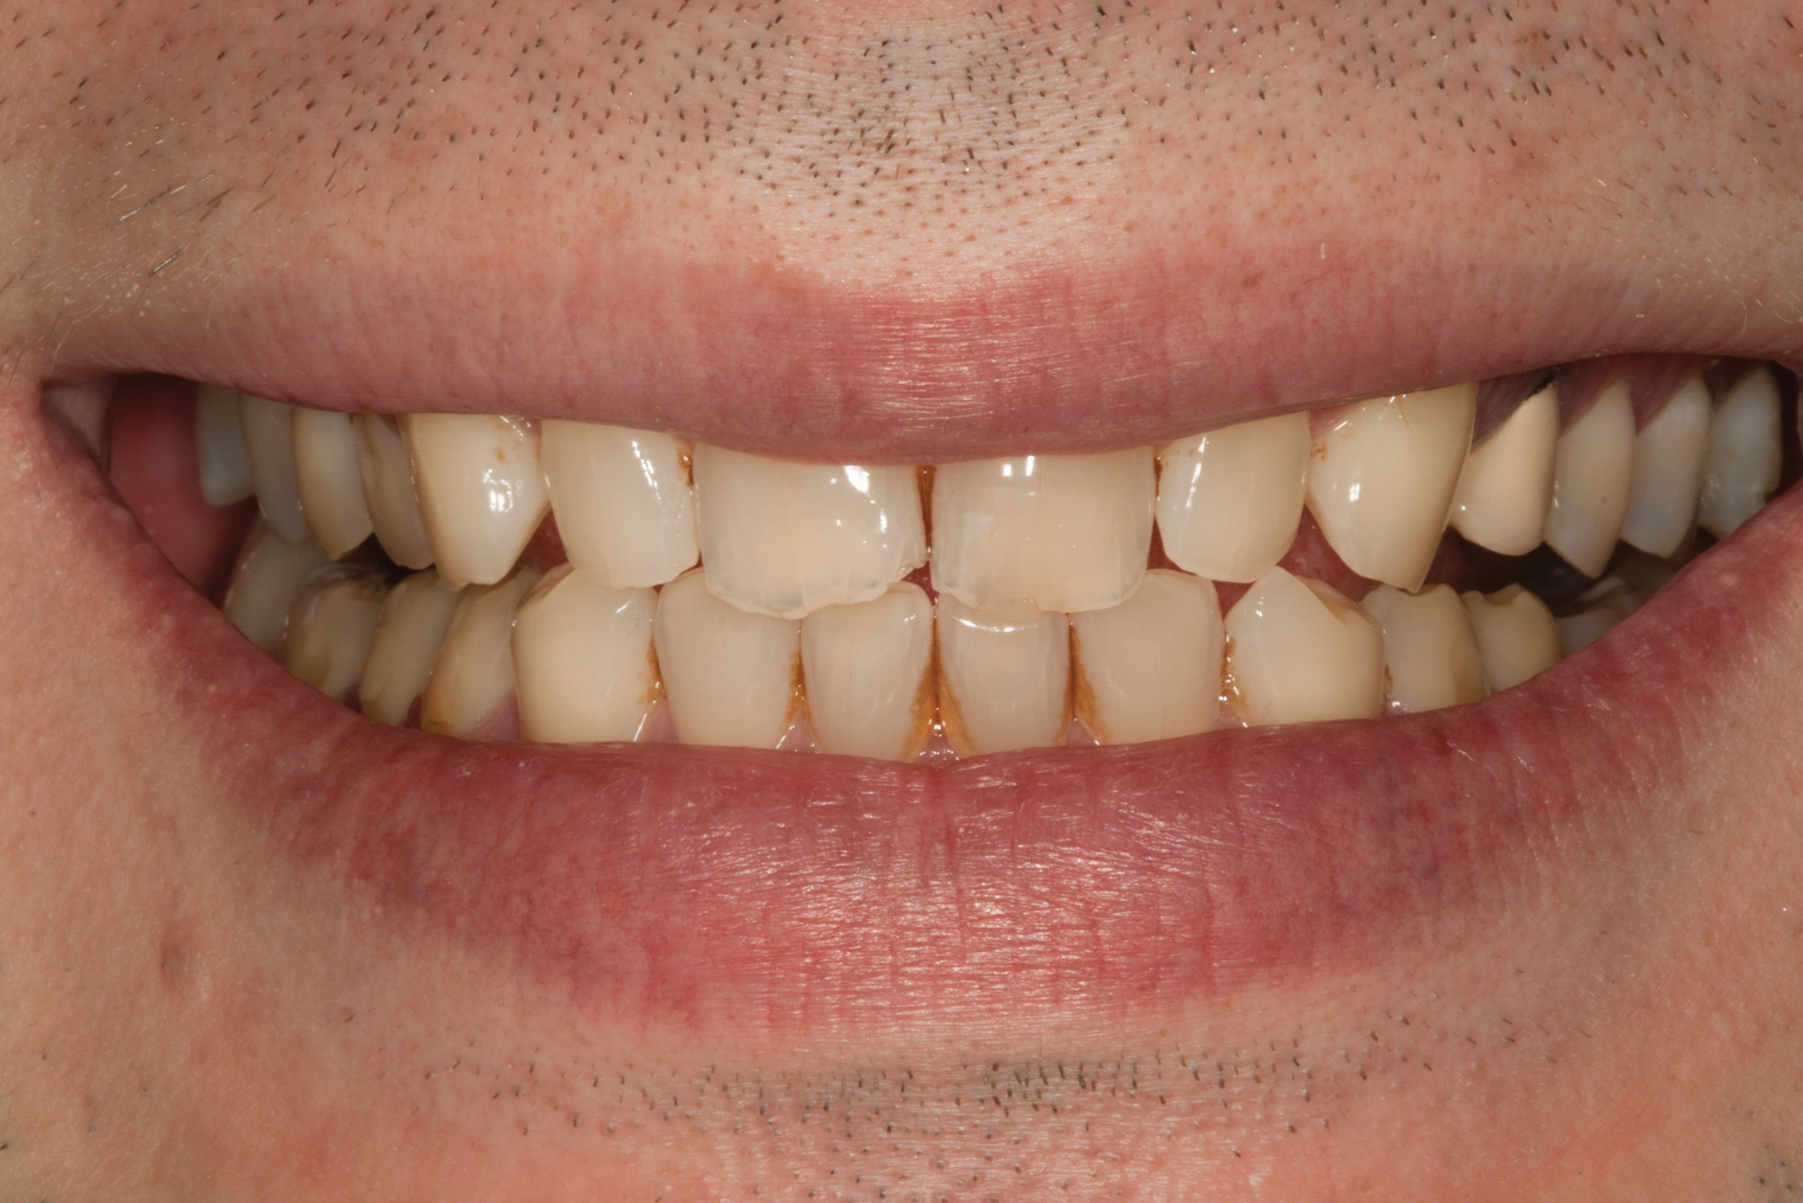

(1.) Preoperative smile photograph.

Figure 1

A 34-year-old male patient with no medical issues presented to the office with the chief complaint of a failing crown on tooth No. 12. The patient was also unhappy with his bite and the appearance of his teeth (Figure 1 and Figure 2).

A comprehensive examination was carried out, and preoperative photographs were taken (Figure 1 through Figure 4). The patient presented with fair oral hygiene and slight, generalized tissue inflammation. Caries and defective restorations were detected on teeth Nos. 4, 5, 13, and 14. The crown on tooth No. 12 was showing signs of leakage, and although the endodontic access cavity had been temporarily restored with composite, this endodontic re-treatment was acceptable and the tooth was otherwise symptom-free. Erosion was present on most of the posterior teeth and the cuspids, and abrasion was noted on teeth Nos. 4, 5, 10, 11, 20, 21, 22, 28, and 29. An examination of the patient's muscles, joints, and bite revealed no joint sounds, a normal range of motion, and negative joint load and immobilization tests.

The dentofacial examination revealed a low smile line with no incisor display when the lips were in repose. The anterior teeth were chipped and worn, and their overall color was darkened. The buccal corridors were deficient, and the failing crown on tooth No. 12 was visible in a full smile.